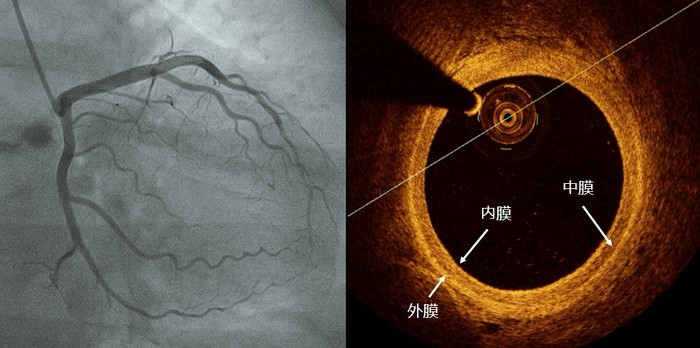

由于OCT的光纤探头很小(比牙签的头端还细),可以放入到血管腔内,同时能实时360°从内部观察血管壁的情况,获得血管内部的图像信息,故有“活体显微镜”之称。它能清晰地显示动脉的内膜、中膜和外膜三层结构。

OCT除能分析血管壁的成分外,还对是否需要植入支架提供有价值的信息。33岁的王先生因心绞痛行冠状动脉造影显示前降支开口80%以上的狭窄。按照既往的经验和策略,王先生需要植入支架。但通过OCT检查发现病变是偏心狭窄,血管腔足够大,仅需要药物治疗就可以,故未植入支架。43岁的陈先生是一位心肌梗死患者,闭塞的冠状动脉经抽吸导管抽吸血栓后,局部狭窄明显减轻,按常规需要植入支架。但经过OCT检查后发现并没有明显狭窄,只是“斑块侵蚀”导致血栓形成而引起血管闭塞,故放弃支架治疗。对于需要支架植入的患者,OCT可以精确测量需植入支架的直径和长度,是精准评估支架植入后效果最有效的工具。如支架是否紧贴血管壁、支架两端是否有血管撕裂等,这一优势是其他工具无法媲美的。47岁的王先生是一位急性心肌梗死患者,通过支架植入前后冠状动脉造影和OCT结果可以明显看出,冠状动脉造影仅能看到血管的轮廓而不能发现血管内病变的性质,而OCT就能一目了然地显示斑块破裂和支架植入后情况,显示支架贴血管壁良好。